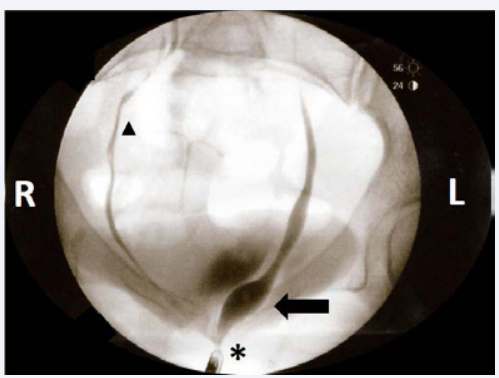

Figure 3 Fluoroscopic imaging of a retrograde cystoscopy details the ureteral orifice of a supernumerary ureter inserting into the proximal portion of the external sphincter muscle of the female urethra (asterisk). The tip of the cystoscope can be seen just inferior and to the left of the asterisk. A significant ureterocele can be observed to be filled with dye (arrow) just proximal to the insertion into the external sphincter muscle of the female urethra. One of the supernumerary ureters for the right collecting system can be observed ascending from the urinary bladder to the right kidney (triangle). The other right ureter was not visualized in this image as the dye from that injection had dissipated.